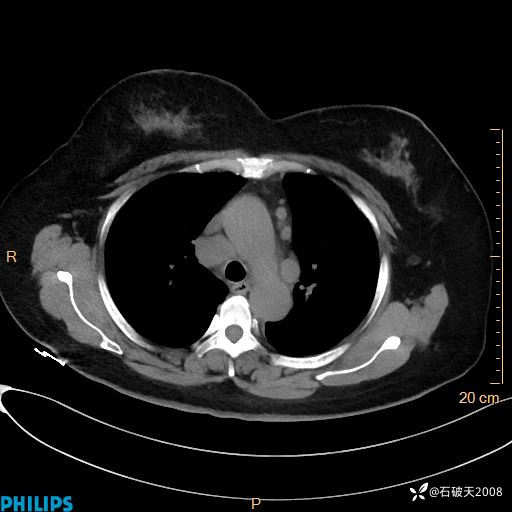

静脉期